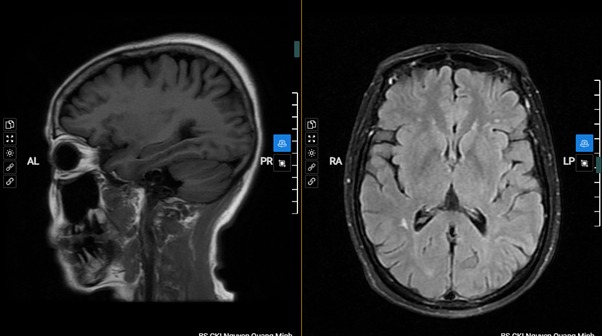

MRI sọ não: Công nghệ hình ảnh chức năng nâng cao này cho phép tạo ra hình ảnh chi tiết của não bộ và có thể phát hiện các vấn đề như khối u, chấn thương, hay bất kỳ biến đổi nào khác.